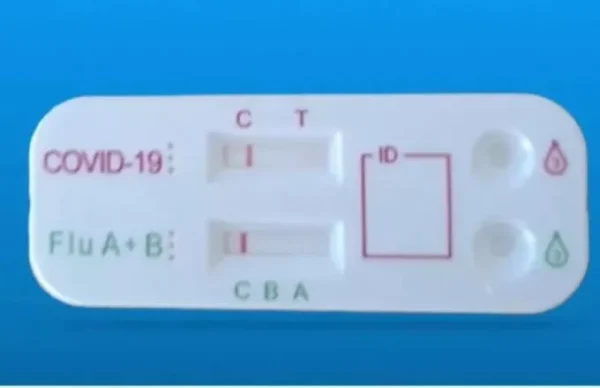

Κορωνοϊός: Συναγερμός από ΠΟΥ για τη νέα παραλλαγή ΧΒΒ.1.5 – Η πιο μεταδοτική μέχρι τώρα

Η υποπαραλλαγή του κορωνοϊού, η ΧΒΒ.1.5 έχει εξαπλωθεί σε 29 χώρες , είναι η κυρίαρχη και είναι η πιο μεταδοτική που έχουμε δεί μέχρι τώρα

Η υποπαραλλαγή του κορωνοϊού, η ΧΒΒ.1.5 έχει εξαπλωθεί σε 29 χώρες , είναι η κυρίαρχη και είναι η πιο μεταδοτική που έχουμε δεί μέχρι τώρα